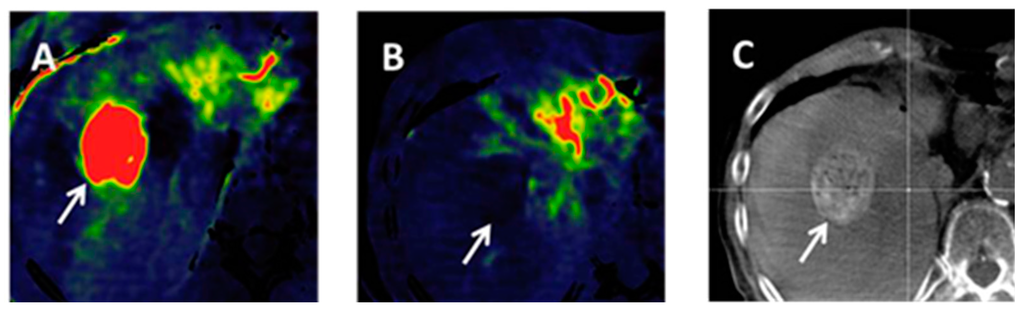

4.3. Volume-Perfusion CT (VPCT)

- Fischer, M.A.; Kartalis, N.; Grigoriadis, A.; Loizou, L.; Stal, P.; Leidner, B.; Aspelin, P.; Brismar, T.B. Perfusion computed tomography for detection of hepatocellular carcinoma in patients with liver cirrhosis. Eur. Radiol. 2015, 25, 3123–3132. [Google Scholar] [CrossRef] [PubMed]

- Ippolito, D.; Bonaffini, P.A.; Capraro, C.; Leni, D.; Corso, R.; Sironi, S. Viable residual tumor tissue after radiofrequency ablation treatment in hepatocellular carcinoma: Evaluation with CT perfusion. Abdom. Imaging 2013, 38, 502–510. [Google Scholar] [CrossRef] [PubMed]

- Kaufmann, S.; Horger, T.; Oelker, A.; Kloth, C.; Nikolaou, K.; Schulze, M.; Horger, M. Characterization of hepatocellular carcinoma (HCC) lesions using a novel CT-based volume perfusion (VPCT) technique. Eur. J. Radiol. 2015, 84, 1029–1035. [Google Scholar] [CrossRef] [PubMed]

- Jiang, T.; Kambadakone, A.; Kulkarni, N.M.; Zhu, A.X.; Sahani, D.V. Monitoring response to antiangiogenic treatment and predicting outcomes in advanced hepatocellular carcinoma using image biomarkers, CT perfusion, tumor density, and tumor size (RECIST). Investig. Radiol. 2012, 47, 11–17. [Google Scholar] [CrossRef] [PubMed]

- Ippolito, D.; Bonaffini, P.A.; Ratti, L.; Antolini, L.; Corso, R.; Fazio, F.; Sironi, S. Hepatocellular carcinoma treated with transarterial chemoembolization: Dynamic perfusion-CT in the assessment of residual tumor. World J. Gastroenterol. 2010, 16, 5993–6000. [Google Scholar] [PubMed]

- Okada, M.; Kim, T.; Murakami, T. Hepatocellular nodules in liver cirrhosis: State of the art CT evaluation (perfusion CT/volume helical shuttle scan/dual-energy CT, etc.). Abdom. Imaging 2011, 36, 273–281. [Google Scholar] [CrossRef] [PubMed]

- Ippolito, D.; Sironi, S.; Pozzi, M.; Antolini, L.; Invernizzi, F.; Ratti, L.; Leone, E.B.; Fazio, F. Perfusion CT in cirrhotic patients with early stage hepatocellular carcinoma: Assessment of tumor-related vascularization. Eur. J. Radiol. 2010, 73, 148–152. [Google Scholar] [CrossRef] [PubMed]